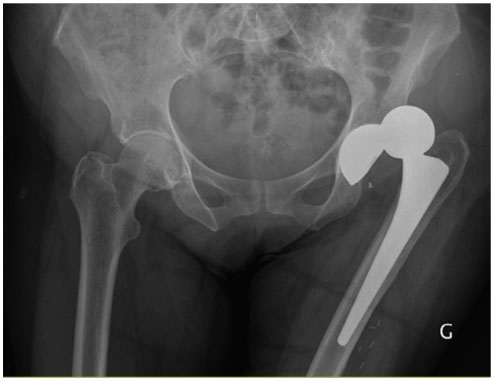

Lorsqu’il sort, il doit s’aider d’une canne que son frère, opéré il y a peu, lui a donnée. Celle-ci le soulage partiellement.